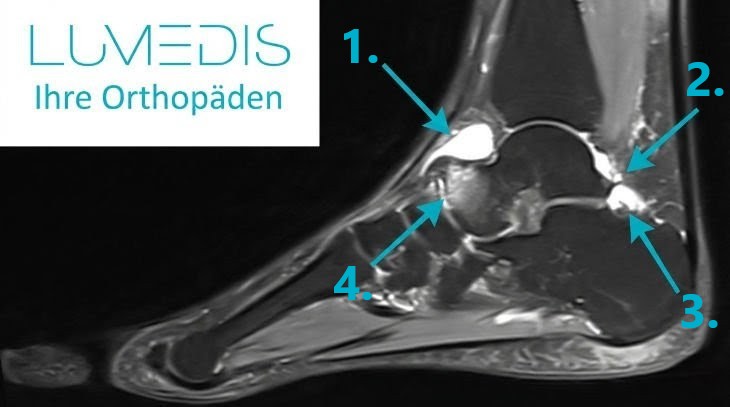

Auch bildgebende Untersuchungen werden mitunter notwendig, um einen Kapselriss des Sprunggelenks herauszufinden und differentialdiagnostische Ursachen auszuschliessen. So kann in einigen Fällen eine Röntgenaufnahme oder eine Magnetresonanztomographie (MRT) durchgeführt werden, um andere mögliche Verletzungen wie Knochenbrüche oder Bänderrisse auszuschließen.

Eine MRT Untersuchung des oberen Sprunggelenks sollte immer dann durchgeführt werden, wenn man vermutet, dass es zu Verletzungen gekommen ist von:

Auch wenn vorangegangen Untersuchungen ohne pathologischen Befund blieben und die Beschwerden im Sprunggelenk noch vorhanden sind, nicht besser oder sogar stärker werden, sollte eine MRT Untersuchung durchgeführt werden.

Eine MRT Untersuchung dauert ca 15 Minuten und stellt die meisten Gewebe des untersuchten Bereichs dar.

Auch nach schweren Unfällen, z.B. nach einem Sturz beim Sport sollte zeitnah eine MRT Untersuchung durchgeführt werden um möglichst schnell einen Überblick über die Verletzungen zu bekommen.